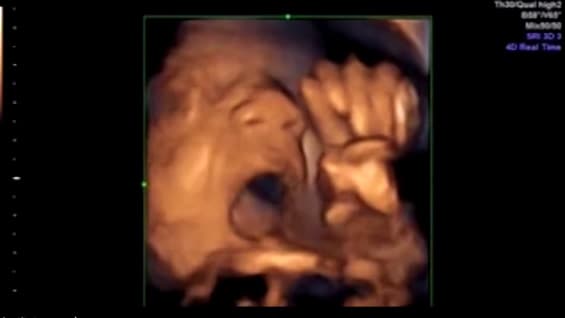

EPS

Médico denuncia abandono del sistema de salud: lleva 20 días sin tratamiento y su estado se deteriora